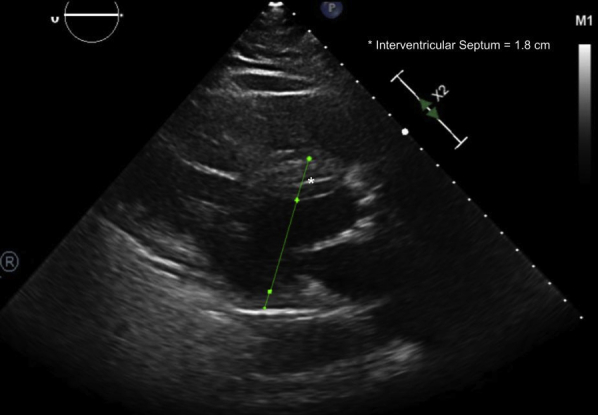

The initial physical examination was significant for an unresponsive man on mechanical ventilation. As per emergency room documentation, initial heart rate after resuscitation was approximately 30 beats/min, with a mean arterial pressure of 60 mm Hg. Cardiac auscultation revealed a slow but regular rhythm with normal S1 and S2 without significant murmurs or gallops. Electrocardiography (ECG) revealed a wide complex rhythm (QRS duration ∼320 ms) with intermittent capture of his pacemaker spikes (2:1 ventricular capture). The ventricular rate by ECG was approximately 40 beats/min (Figure 1A). The patient’s pacemaker interrogation revealed programming of DDDR 70 with increased ventricular thresholds from a baseline of 1 V at 0.4 ms to 1.75 V at 0.4 ms. This threshold was performed several hours after initial resuscitation. Ventricular outputs were 2.5 V at 0.4 ms but increased at the time of interrogation to 4 V to provide a 2:1 safety margin. There were clear episodes of loss of reliable ventricular and atrial capture that seemed to correlate temporally to the presumed time of the patient’s arrest (Figure 2). These events were incidentally captured as automatic mode switching events because of lack of capture and oversensing in the atrial channel. Thus, we did not know the nadir ventricular rate during arrest. No ventricular arrhythmias were detected. The initial lactic acid on admission was 6.4 with a pH of 7.05 and bicarbonate of 20 mmol/l; he subsequently developed acute renal failure. His initial flecainide level was elevated to 2.44 μg/ml, which was more than twice the upper limit of normal (0.99 μg/ml). Echocardiography after resuscitation showed an ejection fraction of 20% to 25% with marked asymmetric LVH, with a measured interventricular septum of 1.8 cm (Figure 3). Marked mechanical ventricular dyssynchrony was present (Video 1). Coronary angiography showed no evidence of obstructive coronary artery disease.

Figure 3.

Echocardiogram After Arrest

The parasternal long-axis view of the left ventricle shows marked asymmetric left ventricular hypertrophy. The interventricular septum measures 1.8 cm.